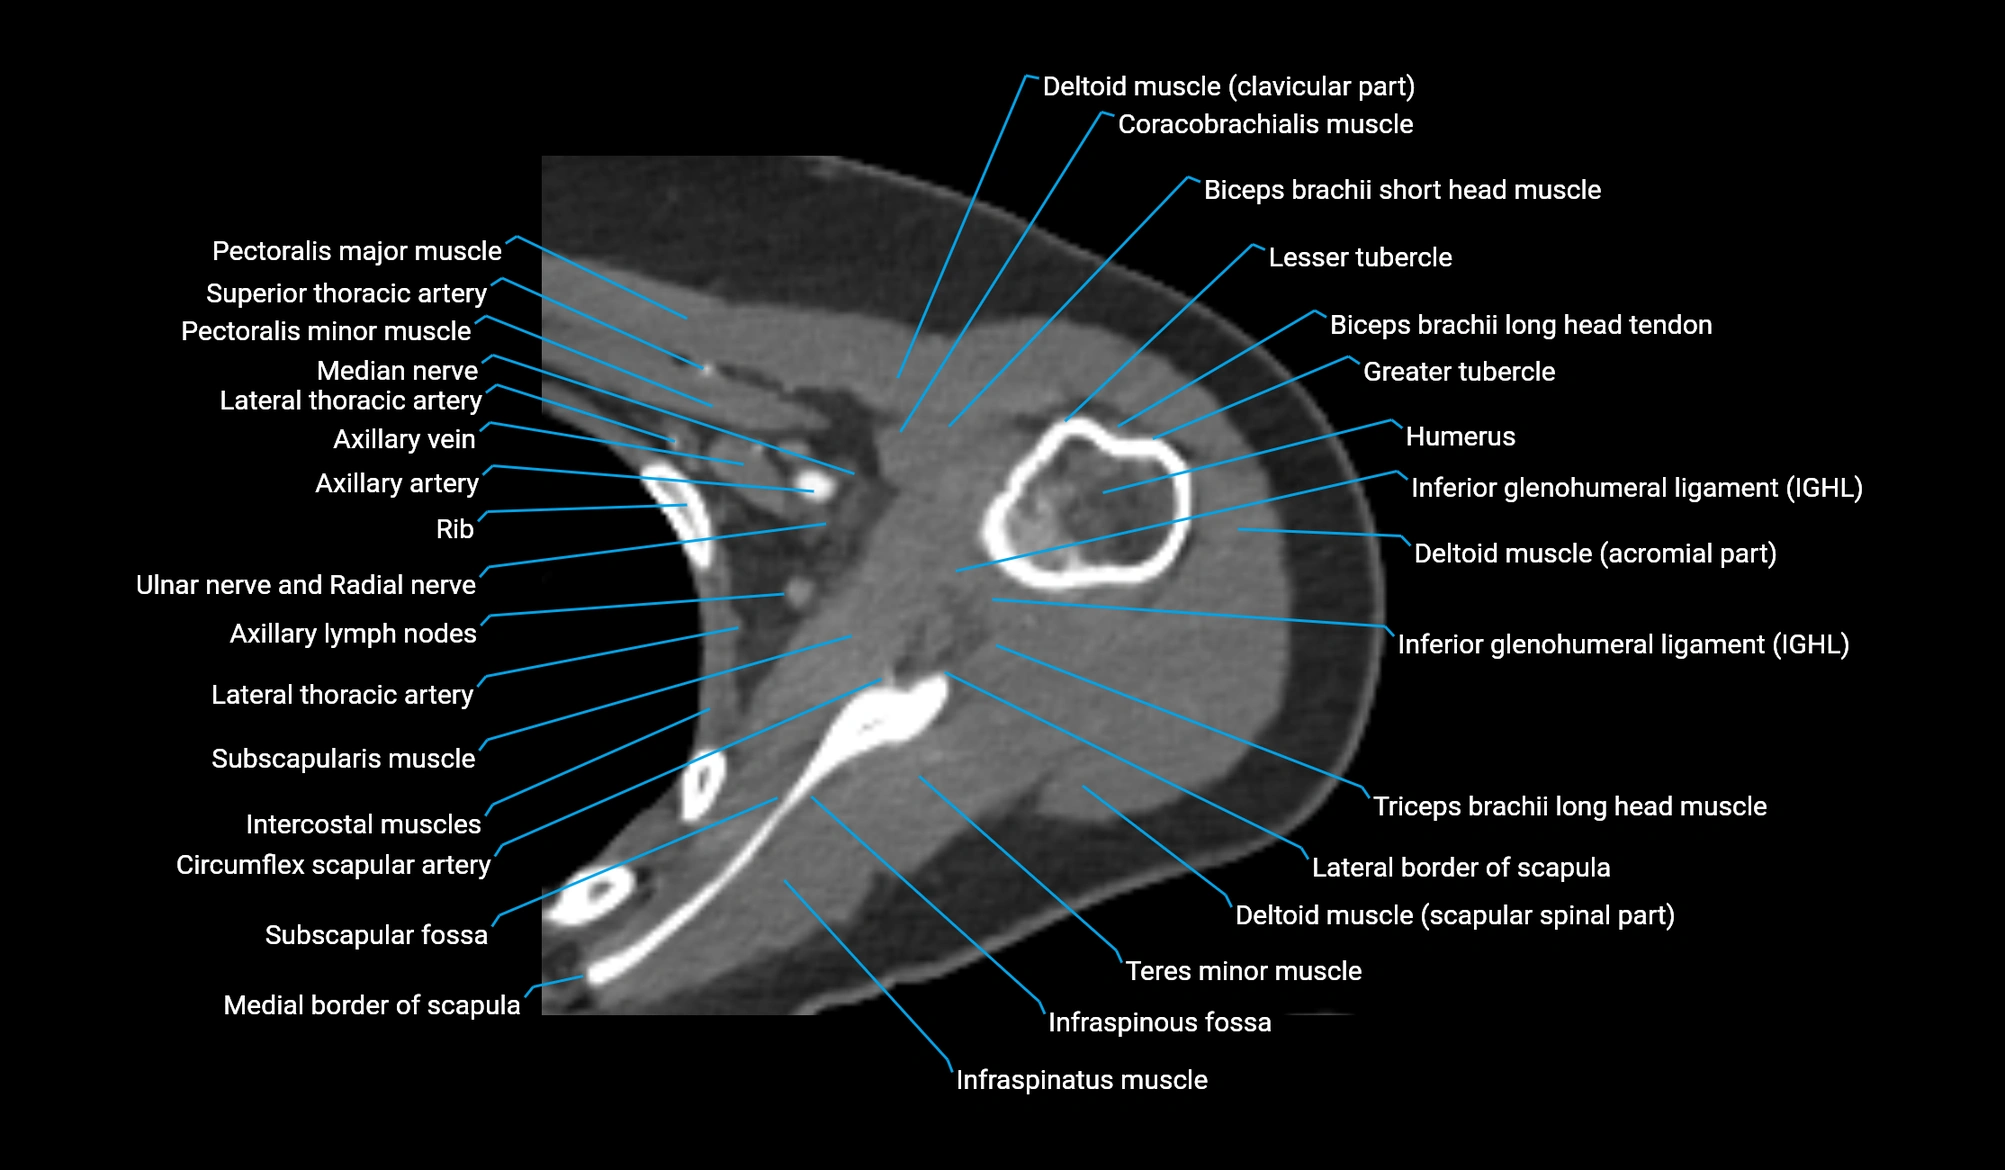

- Head of humerus

- Greater tubercle of humerus

- Lesser tubercle of humerus

- Glenoid labrum

- Inferior glenohumeral ligament

- Subscapularis muscle

- Infraspinatus muscle

- Teres minor muscle

- Coracobrachialis muscle

- Clavicular part of deltoid muscle

- Scapular spinal part of deltoid muscle

- Lateral border of scapula

- Medial border of scapula

- Subscapular fossa

- Pectoralis major muscle

- Pectoralis minor muscle

- Axillary lymph nodes

- Circumflex scapular artery